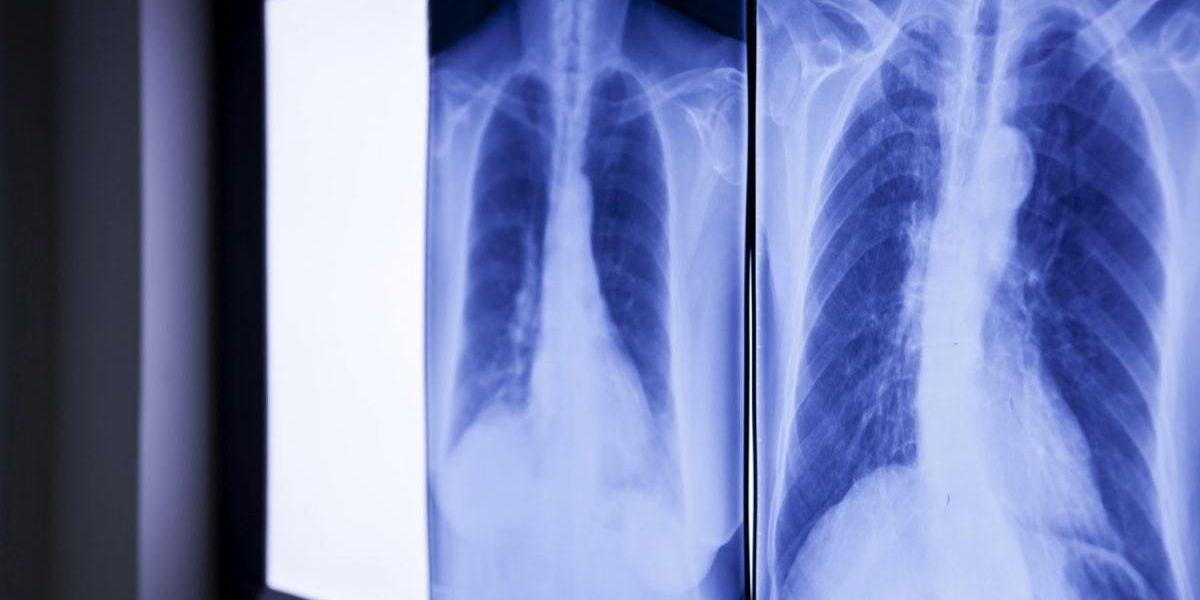

Wang, în vârstă de 32 de ani, s-a prezentat la o unitate medicală din Wenzhou, acuzând dureri abdominale persistente. Investigațiile medicale au dezvăluit existența unui obiect străin în duoden, suspectat a fi un termometru cu mercur. Radiografiile au confirmat suspiciunile, indicând prezența termometrului în interiorul corpului. Situația era cu atât mai alarmantă cu cât vârful dispozitivului apăsa pe peretele intestinal, crescând riscul de perforație și hemoragie internă severă.